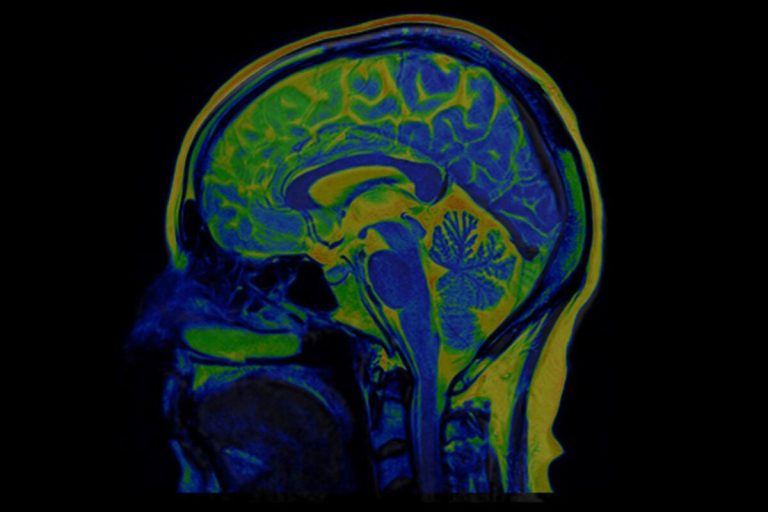

One of the first spectroscopic imaging-based studies of neurological injury in COVID-19 patients has been reported by researchers at Harvard-affiliated Massachusetts General Hospital (MGH) in the American Journal of Neuroradiology. Looking at six patients using a specialized magnetic resonance (MR) technique, they found that COVID-19 patients with neurological symptoms show some of the same metabolic disturbances in the brain as patients who have suffered oxygen deprivation (hypoxia) from other causes, but there are also notable differences.

It is thought that the disease’s primary effect on the brain is through hypoxia, but few studies have documented the specific types of damage that distinguish COVID-19-related brain injury. Several thousand patients with COVID-19 have been seen at the MGH since the outbreak began early this year, and this study included findings from three of those patients.

The researchers used 3 Tesla Magnetic Resonance Spectroscopy (MRS), a specialized type of scanning that is sometimes called a virtual biopsy. MRS can identify neurochemical abnormalities even when structural imaging findings are normal. COVID-19 patients’ brains showed N-acetyl-aspartate (NAA) reduction, choline elevation, and myo-inositol elevation, similar to what is seen with these metabolites in other patients with white matter abnormalities (leukoencephalopathy) after hypoxia without COVID. One of the patients with COVID-19 who showed the most severe white matter damage (necrosis and cavitation) had particularly pronounced lactate elevation on MRS, which is another sign of brain damage from oxygen deprivation.

Two of the three COVID-19 patients were intubated in the intensive care unit at the time of imaging, which was conducted as part of their care. One had COVID-19-associated necrotizing leukoencephalopathy. Another had experienced a recent cardiac arrest and showed subtle white matter changes on structural MR. The third had no clear encephalopathy or recent cardiac arrest. The non-COVID control cases included one patient with white matter damage due to hypoxia from other causes (post-hypoxic leukoencephalopathy), one with sepsis-related white matter damage, and a normal, age-matched, healthy volunteer.

“A key question is whether it is just the decrease in oxygen to the brain that is causing these white matter changes or whether the virus is itself attacking the white matter,” says MGH neuroradiologist Otto Rapalino, who shares first authorship with Harvard-MGH postdoctoral research fellow Akila Weerasekera.

Compared to conventional structural MR imaging, “MRS can better characterize pathological processes, such as neuronal injury, inflammation, demyelination, and hypoxia,” adds Weerasekera. “Based on these findings, we believe it could be used as a disease and therapy monitoring tool.”